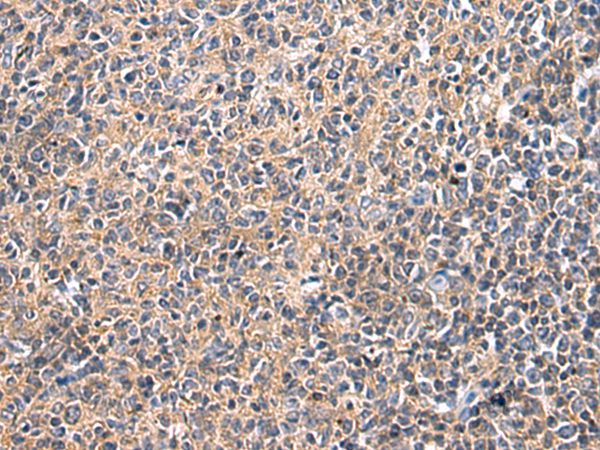

IHC positive control:

Human colorectal cancer and Human esophagus cancer

IHC Recommend dilution:

25-100